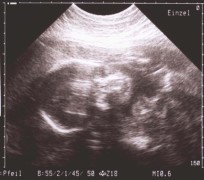

Ultraschall und seine Anwendung